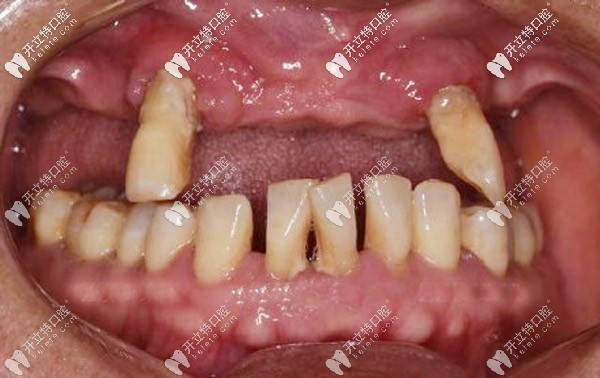

周老先生十多年前先后缺失了三四顆牙后鄰牙就開始晃動,直到今年年初,上頜的牙齒只剩下兩顆,吃飯也受到影響才去牙科看牙。

“很多老人口腔情況跟我一樣,覺得掉牙不是什么事兒,即使旁邊的牙松動了,也是能拖就拖,疼了就吃點消炎藥,誰知道這樣一拖問題”

周老先生后悔地說,自己年輕的時候就是太輕視缺牙,沒有及時修復,才導致現(xiàn)在的牙齒松動,東西都得拿手掰著吃,根本不敢拿牙咬。